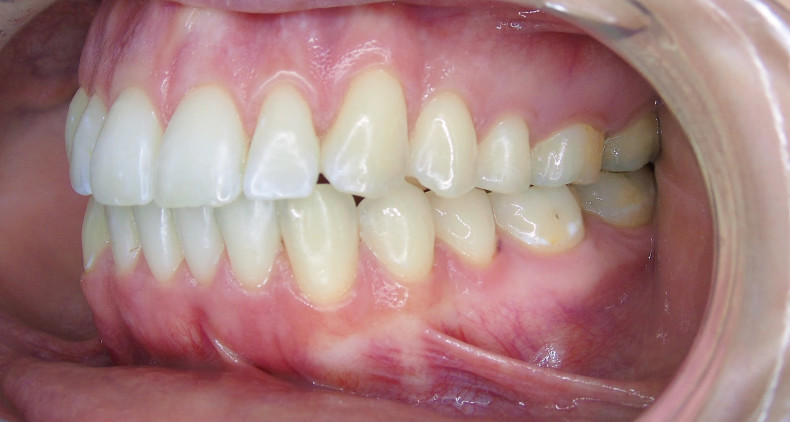

Nach viereinhalb Monaten konnten die Attachments planmäßig entfernt werden.

Aufgrund der latenten Zungendysfunktion war ein stabiles Rezidivkonzept obligatorisch. Deshalb wurden in beiden Kiefern Sechs-Punkt-Retainer geklebt und zusätzliche Retentionsschienen angefertigt. Okklusion und ästhetisches Erscheinungsbild konnten relevant verbessert werden.

Sechs Monate nach Abschluss der Therapie besteht weiterhin ein stabiles Ergebnis. Wie im Vergleichsbild (Abb. 5a–c) zu sehen ist, konnte die geplante vertikale Korrektur vollständig erzielt und die Mittellinie bis auf eine MLV von 1 mm nach rechts im UK korrigiert werden.

Somit kann gezeigt werden, dass auch ohne operativen Eingriff oder festsitzende Apparaturen in kürzester Zeit ein ästhetisch und funktionell zufriedenstellendes Ergebnis erzielt werden kann (Abb. 6a–c; Abb. 7a–e). Es wird daher nachvollziehbar dargestellt, dass bei entsprechender Indikation Aligner für die Behandlung frontal offener Bisse eine hervorragende Alternative zu den konventionellen Behandlungsmethoden sein können. Voraussetzung für diesen Therapieansatz ist ein motivierter Patient mit guter Compliance.